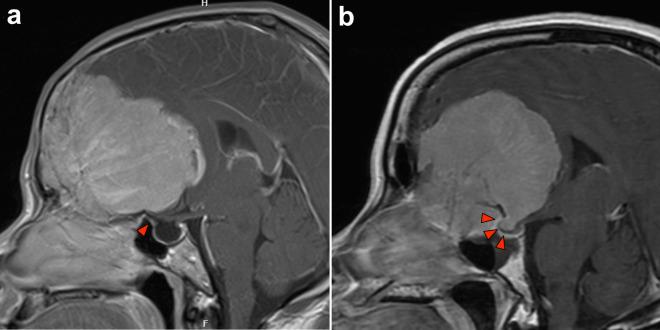

There is a lack of available data regarding the incidence and characteristics of optic canal invasion (OCI) in large midline non-tuberculum sellae anterior skull base meningiomas (NTSAM), specifically those originating predominantly from the olfactory groove and planum sphenoidale. This study aims to describe the incidence and characteristics of OCI as well as clinical and visual outcomes following extensive tumor resection with optic canal exploration in intra-optic canal tumor removal. In addition, the predictive performance of OCI by preoperative magnetic resonance imaging (MRI) is investigated.

MATERIALS AND METHODS

From 2016 to 2024, we retrospectively reviewed 24 patients with large midline NTSAM who underwent extensive tumor resection in our institution. The OCI was evaluated and compared between preoperative MRI and intraoperative findings. The OCI was classified as follows. Type 1 represented no invasion, type 2 represented secondary invasion, type 3 represented partial wall invasion (two subtypes), and type 4 represented invasion into the superior-medial-inferior walls of the optic canal. Visual functions were assessed before and after surgery.

RESULTS

Among 24 patients, a mean tumor size of 57.2 mm (range 39.0-79.0). The OCI was observed intraoperatively in 22 cases (91.7%), with 19 cases exhibiting bilateral OCI. Among the 48 optic canals in the 24 patients, 18 (37.5%) were type 4, 12 (25.0%) were type 3-inferomedial, 9 (18.8%) were type 3-superomedial, and 2 (4.2%) were type 2, where 7 (14.6%) optic canals were without OCI. A significant correlation was observed between intraoperative OCI and the tumors that exhibited involvement of the tuberculum sellae (TS) on MRI (p < 0.001). For patients with visual impairment, the vision in 27 of 38 (71.1%) eye sides showed improvement following the surgery. There was 1 (4.2%) case of tumor recurrence at the mean follow-up time of 27.3 months (range 4-73 months).

CONCLUSIONS

A high incidence of OCI was observed in the large midline NTSAM. The identification of TS involvement on MRI can serve as a strong predictor of OCI. Therefore, optic canal exploration to remove the optic canal invasion during the surgical removal of these particular tumors should be contemplated to attain radical tumor resection to enhance the possibility of improving visual function and reduce the risk of recurrence.

关于大型中线非蝶骨嵴鞍结节前颅底脑膜瘤(NTSAM),特别是主要起源于嗅沟和蝶骨平台的脑膜瘤,视神经管侵犯(OCI)的发生率和特征的可用数据匮乏。本研究旨在描述OCI的发生率和特征,以及在视神经管内肿瘤切除术中进行广泛肿瘤切除并探查视神经管后的临床和视觉结果。此外,还研究了术前磁共振成像(MRI)对OCI的预测性能。

材料与方法

2016年至2024年,我们回顾性分析了在我院接受广泛肿瘤切除的24例大型中线NTSAM患者。对视神经管侵犯情况在术前MRI和术中发现之间进行评估和比较。OCI分类如下。1型表示无侵犯,2型表示继发性侵犯,3型表示部分壁侵犯(两个亚型),4型表示侵犯视神经管的上、中、下壁。在手术前后评估视觉功能。

结果

24例患者中,肿瘤平均大小为57.2mm(范围39.0 - 79.0mm)。术中观察到22例(91.7%)存在OCI,其中19例为双侧OCI。在24例患者的48条视神经管中,18条(37.5%)为4型,12条(25.0%)为3型 - 下内侧型,9条(18.8%)为3型 - 上内侧型,2条(4.2%)为2型,7条(14.6%)视神经管无OCI。术中OCI与MRI显示累及蝶骨嵴(TS)的肿瘤之间存在显著相关性(p < 0.001)。对于有视力障碍的患者,38只患眼中有27只(71.1%)术后视力改善。在平均随访时间27.3个月(范围4 - 73个月)时,有1例(4.2%)肿瘤复发。

结论

在大型中线NTSAM中观察到OCI的高发生率。MRI上TS受累的识别可作为OCI的有力预测指标。因此,在手术切除这些特定肿瘤时,应考虑探查视神经管以去除视神经管侵犯,以实现肿瘤的根治性切除,提高改善视觉功能的可能性并降低复发风险。